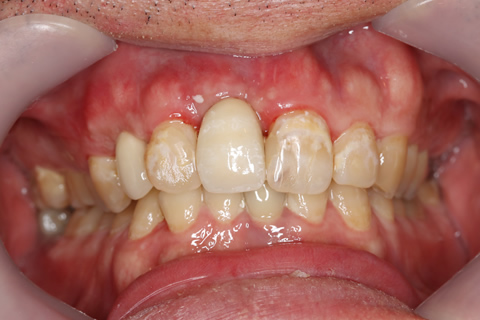

症例5

治療前

インプラント埋入時

治療後

- 年齢・性別

- 35歳男性

- 治療期間

- 3ヶ月

- 抜歯

- 右上1.3左上6.7の残根抜歯

- 治療費

- 123.2万円

- 備考

- 右上1.3左上6.7の欠損部

- 治療内容

- 4本のインプラントを一回のオペで埋入。

- 施術の副作用(リスク)

- オペによる知覚障害。インプラントによる歯肉炎。インプラント脱落。